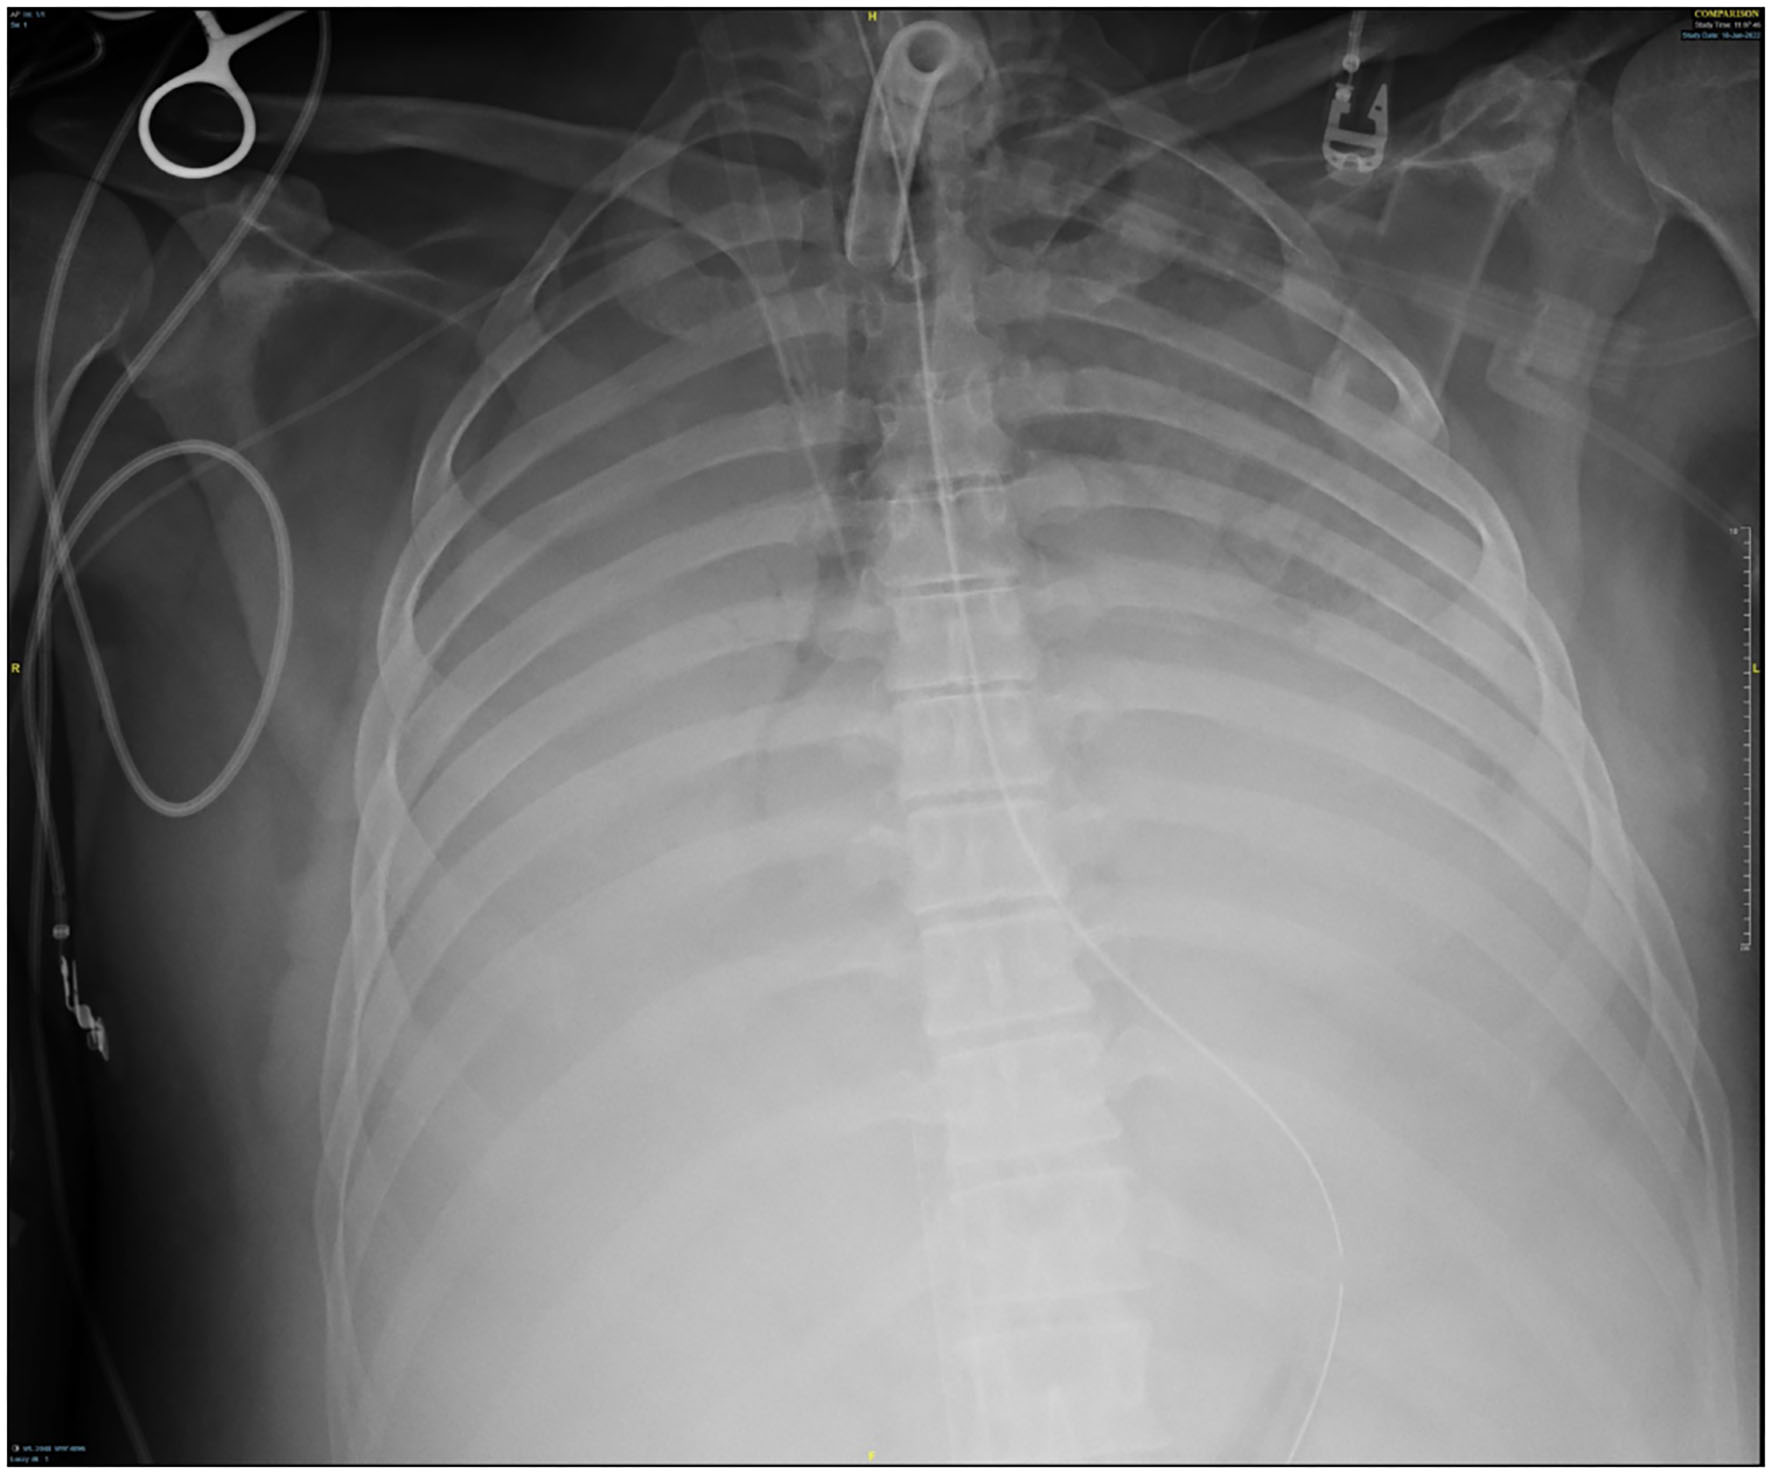

Figure 4

Chest x-ray off ventilator support.

Given adequate oxygenation, the decision was made to temporarily discontinue mechanical ventilation post-bronchoscopy to allow clot formation in the tracheobronchial tree. Paralysis was reinitiated to minimize oxygen consumption. Systemic anticoagulation and antiplatelet therapy were discontinued to promote clot formation. Due to the presence of VV ECMO, HemoSphereTM (Edwards Lifesciences, Irvine, CA) technology with near-infrared tissue oximetry was utilized to sustain adequate cerebral and somatic saturation. Goals were set to maintain regional cerebral saturation >60% and somatic tissue saturation >50% for each lower extremity. Cardiac hemodynamics were evaluated non-invasively via FloTracTM (Edwards Lifesciences, Irvine, CA) monitoring system, with a goal cardiac index of 2.5 L/min/m2.

Though active hemorrhage had ceased during this time of mechanical ventilation, the patient's chest x-ray continued to exhibit bilateral opacification (Figure 4). On hospital day #20 (VV ECMO day #13), a repeat bronchoscopy was performed to remove clot which had formed from the bilateral bronchi with some radiographic progress. Due to improvement in active hemoptysis, the ventilator was restarted with a minimum TV of 250 cc (IBW x 4 cc) after 48 hours of complete discontinuation of ventilator. Serial declotting bronchoscopies were then performed utilizing various bronchoscopic instruments including a basket, biopsy clamp, and brush to facilitate clot retrieval. This process was continued daily until all visible clot was removed and chest x-ray demonstrated decreased opacification (Figure 5). Bronchoscopy was performed a total of 14 times. Antiplatelet therapy was then resumed, and there was no recurrence of bronchial hemorrhage, although systemic heparin and anti-platelet agents were held.